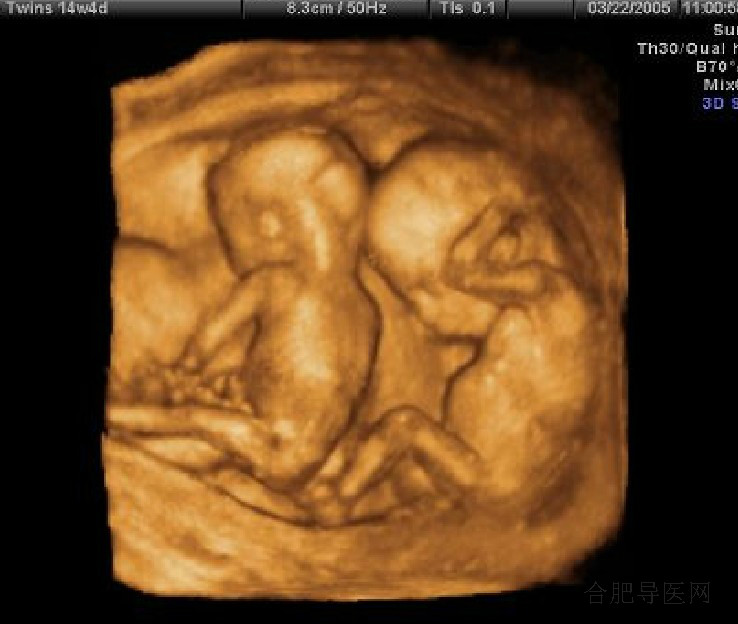

四维彩超会给胎儿带来安全风险吗

四维彩超会给胎儿带来安全风险吗 在我们医生这里,没有四维的说法,准确的说法应该是实时…[详情]